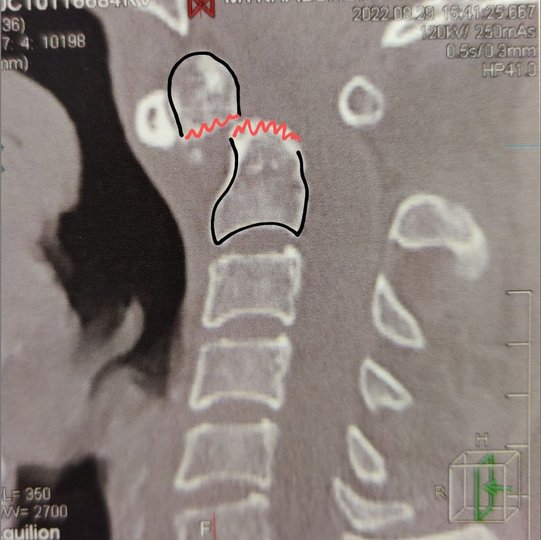

Про проведення операції Рівненська обласна клінічна лікарні імені Семенюка повідомила в понеділок, 12 вересня. Відомо, що пацієнту 46 років, він травмувався ще в 1997 році. У нього був зламаний один з головних стабілізаційних елементів шийно-потиличної ділянки: відросток другого шийного хребця. Чоловікові пощастило, адже спинний мозок первинно не постраждав. Проте через 25 років почали проявлятись симптоми.

Суть операції полягає у тому, що перший і другий шийні хребці вправляються та фіксуються між собою гвинтово-стрижневою конструкцією. Це оперативне втручання на шийному відділі хребта вважається одним із найскладніших через близьке розташування життєво важливих структур таких, як хребетна артерія, пошкодження якої може призвести до інсульту у вертебро-базилярному басейні, та шийний відділ спинного мозку, травма якого може стати причиною глибокої інвалідизації чи смерті пацієнта, – йдеться у повідомленні.